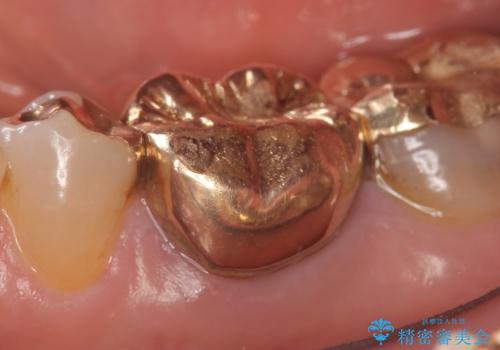

- 左下の奥歯が激しく痛むので診て欲しいといらっしゃった方の症例です。

他院で相談したところ抜歯を提案されたが、歯を抜かずに済む方法はないかと当院にいらっしゃいました。

検査の結果左下6に根尖病変を認めたため、再根管治療を行いました。